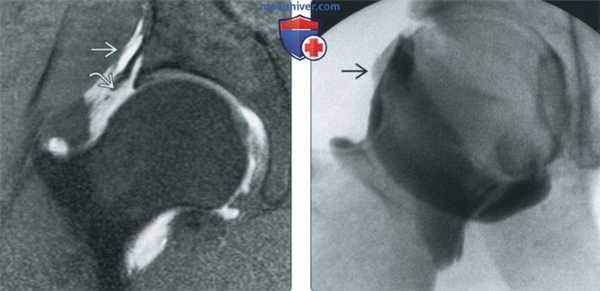

(Слева) МР-артрография в режиме Т1ВИ FS, косоаксиальный срез, пациент с жалобами на рецидив боли после артроскопической коррекции разрыва суставной губы и резекции костного выступа: определяется, что восстановленный участок суставной губы имеет выражено неравномерный контур, однако является интактным, о чем свидетельствует отсутствие затека контраста в суставную губу. Для выявления рецидивирующего разрыва суставной губы лучше выполнить МР-артрографию в режиме Т1ВИ.

(Справа) МР-артрография в режиме Т1ВИ FS, косоаксиальный срез, этот же пациент: выявляется отслоение суставной губы ниже восстановленного участка. Область, подвергшаяся остеохондропластике, ничем не примечательна. (Слева) МР-артрография в режиме Т2ВИ FS, коронарный срез, этот же пациент: суставная капсула растянута, восстановленный участок суставной губы имеет неровный контур и содержит зону, интенсивность сигнала которой соответствует интенсивности сигнала от жидкости. Для дифференциации грануляционной ткани и контрастного препарата в разрыве суставной губы, необходим режим Т1.